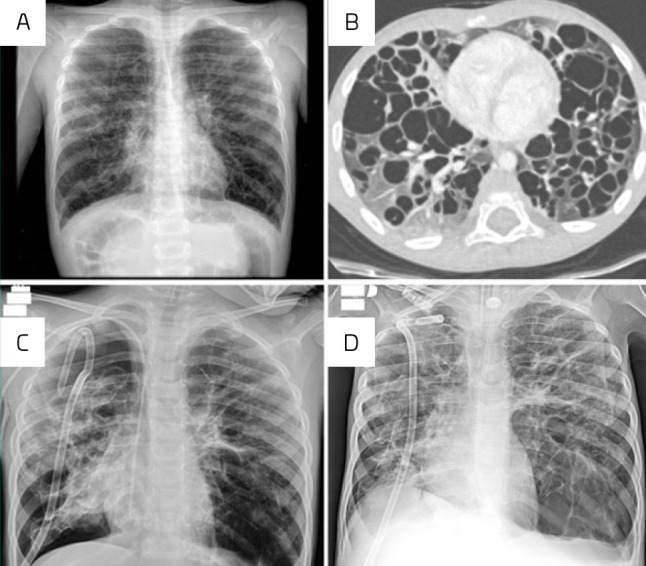

Case description: Case #1: A 3-year-old male patient with a sudden episode of spontaneous right-sided pneumothorax, surgically drained. After 2 months, he experienced two new episodes of contralateral pneumothorax. A pulmonary lymph node biopsy revealed the diagnosis of LCH. He underwent bilateral video-assisted thoracic surgery and mini-thoracotomy with mechanical pleurodesis, in addition to chemotherapy, requiring prolonged hospitalization. Case #2: A 4-year-old boy with progressive dyspnea and wheezing for 5 months. A pulmonary biopsy revealed LCH. He developed significant respiratory distress and right pneumothorax, requiring drainage. Silver nitrate pleurodesis and different chemotherapy regimens were performed. Both patients responded well to multiple chemotherapy treatments, surgeries, and intensive care support.